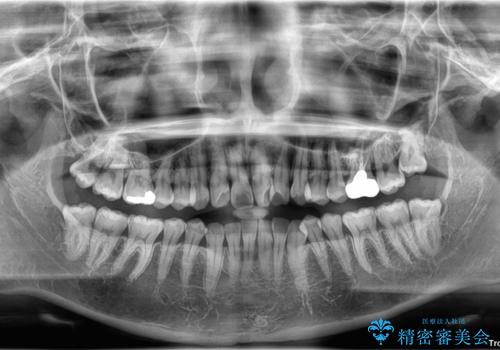

診察の結果、上下の前歯部に**叢生(そうせい/歯のガタガタ・重なり)**が認められました。

特に上の前歯にはねじれや重なりがあり、審美的にも清掃性にも影響している状態でした。

また、上顎前歯の重なっていた部分にはむし歯が見つかり、治療中に適切な処置を行っています。